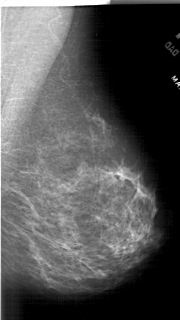

A_1905_1.RIGHT_MLO

RIGHT_CC LINES 5821 PIXELS_PER_LINE 3166 BITS_PER_PIXEL 12 RESOLUTION 43.5 NON_OVERLAY